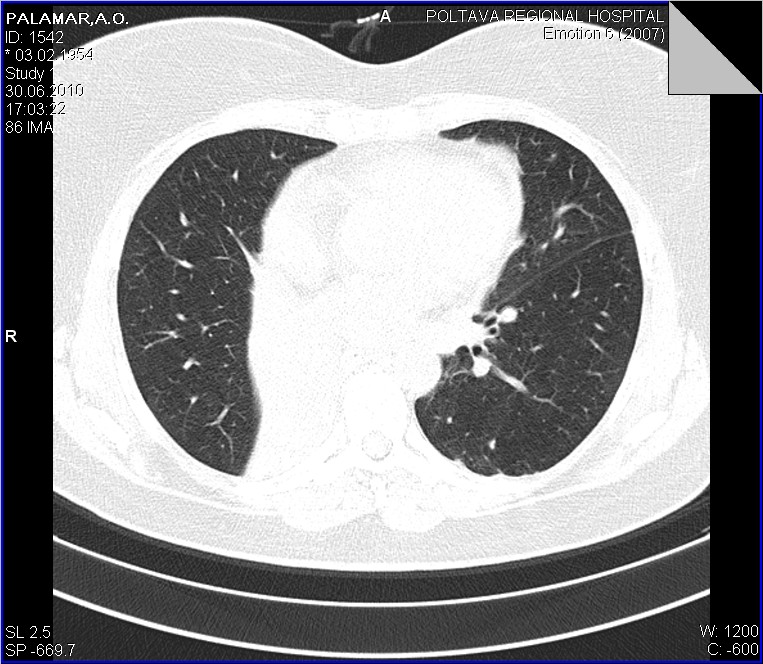

Беседую с пациенткой...да кишечные проблемы были, уже прошли...около 6-8 ми месяцев назад болеела (основная жалоба - кашель), лечилась, в т.ч. стационарно, обследовалась, в т.ч  КТ в ООД - сказали все нормально...живите мол и дальше. Данные предыдущих исследований обещают доставить с понедельника, будем и сами ее докручивать. Ваше мнение, коллеги?

Повторюсь еще раз со сканами, несколько полнее. Конечно, это уже не столь принципиально, но, как по мне, ни С6, ни средней доли нет...Давайте просмотрим еще раз.

Со сканами-то ясность полная. Нет бронха средней доли и шестого. Метод, конечно, превосходный, но и качество снимков имеет огромное значение.

1.Плеврит, как рабочий диагноз тоже пристутсвовал

2. Никтои не спорит, что он, в какой то мере есть, о незначительном количестве "густой" жидкости говорят и УЗИсты

3. Но куда деть "культю" промежуточного бронха? и при чем тогда тут (по отношению к культе) плеврит? Неужели он в состоянии сдавить такой бронх?

1. Спасибо за ссылку, одна из "картинок" полностью повторяет выставленной наблюдение. 2. А теперь о "гвозде", который мне забили пять минут назад "между глазиков". После того, как я переколотил всю хирургию, последняя взялась рьяно выяснять все о больной. Имеется у нее рак матки 4-й степени, состоит она на учете в ООД по этому поводу, все остальные изменения вторичные..... Вот такой случай с ургентности...или о приемственности в наше время...